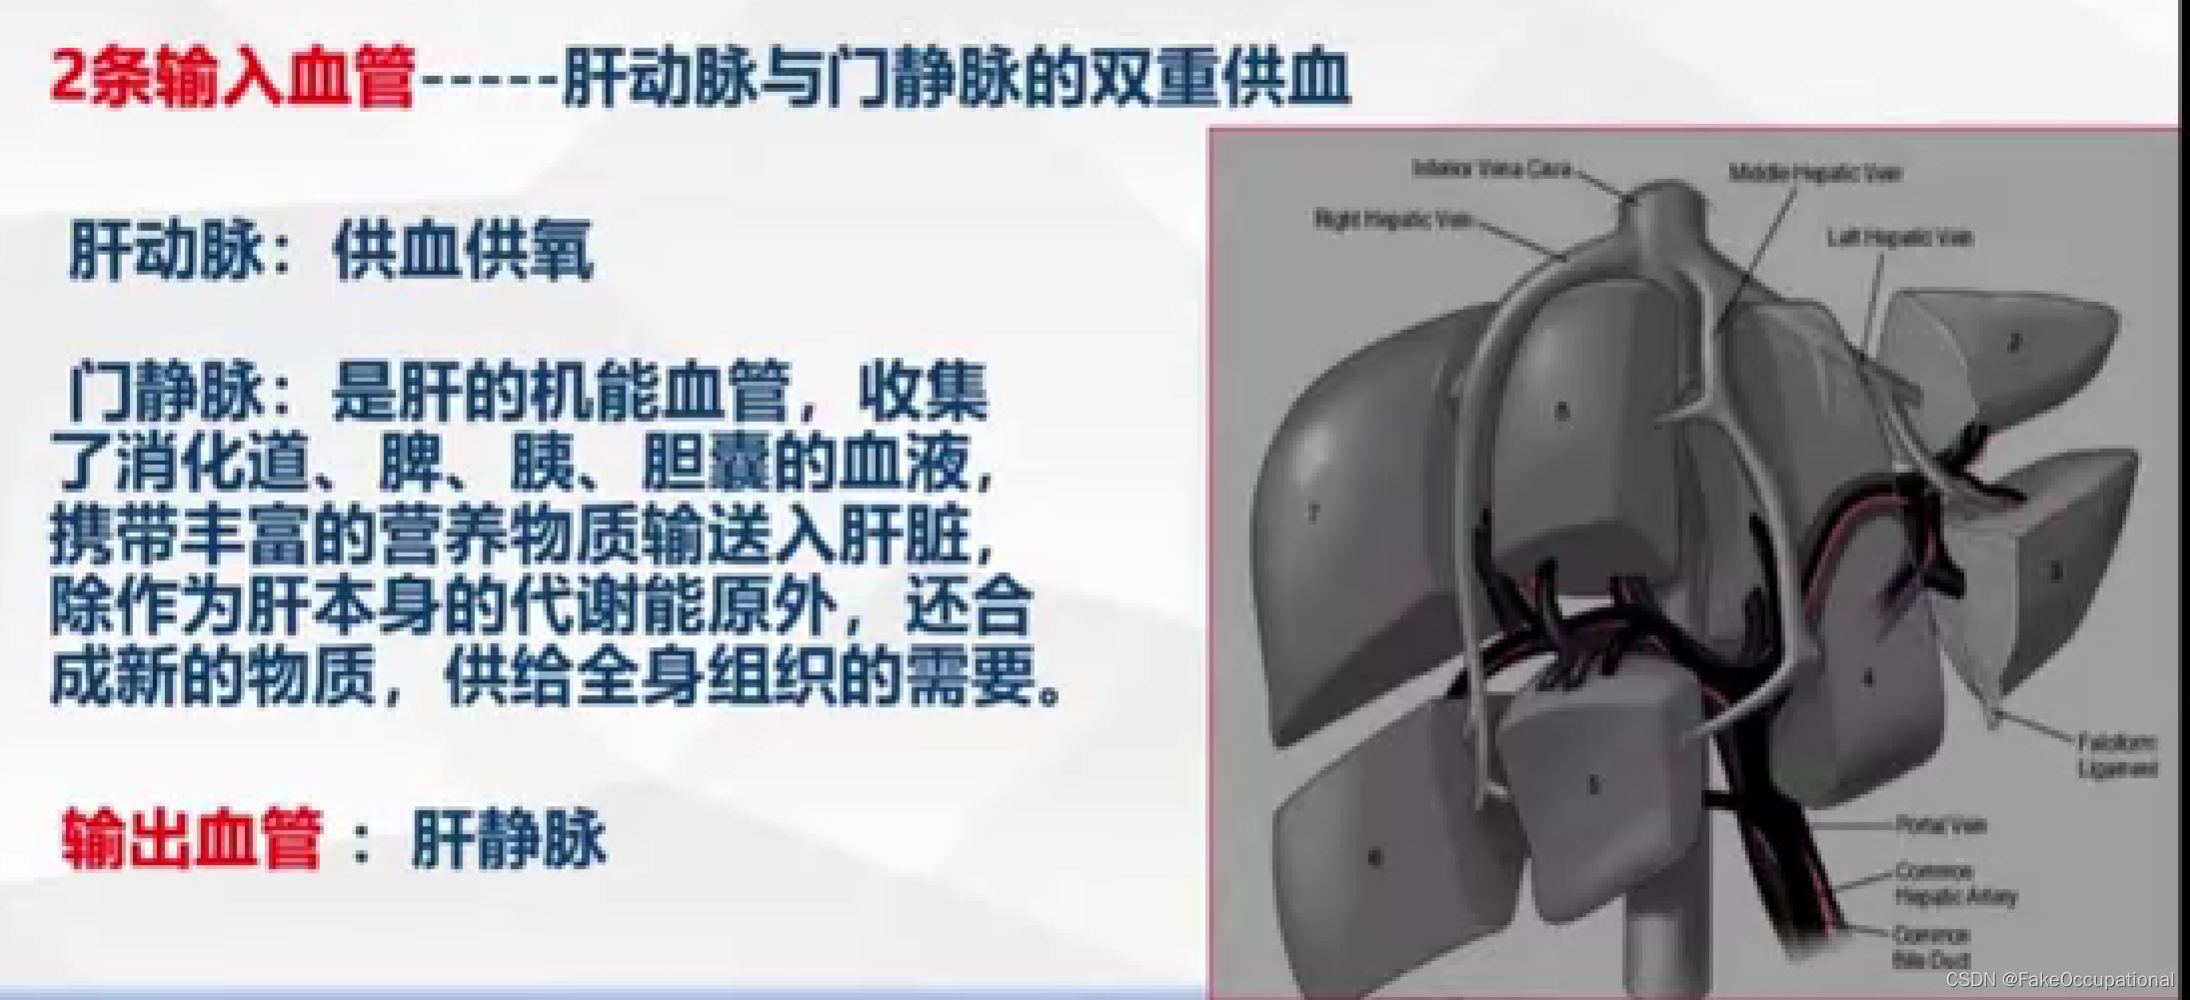

肝脏解剖概要